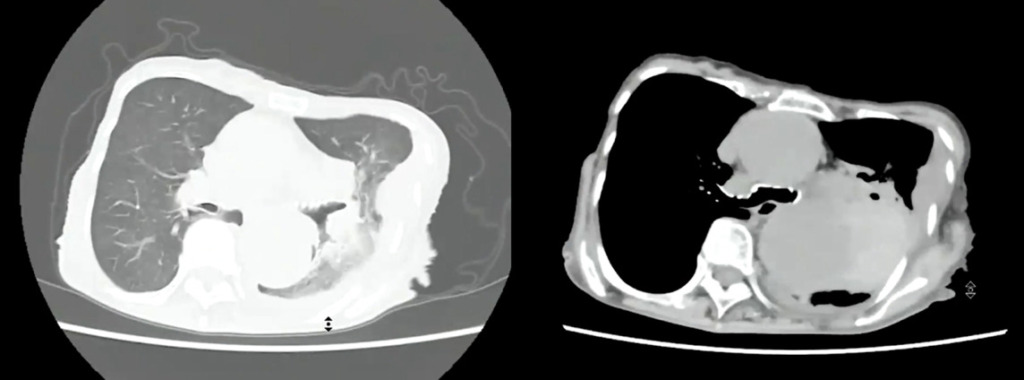

• CT所見

左肺に胸水を認めます。

大動脈が上行~下行まで拡張しています。

独歩にてCT室へ入室し、検査後車椅子に移乗し廊下で待機。(痛みを聞いても痛くはないと返事あり。)

単純CTで胸部大動脈瘤破裂疑いとなり、放射線科医指示のもとストレッチャーで救急外来へ移動しました。